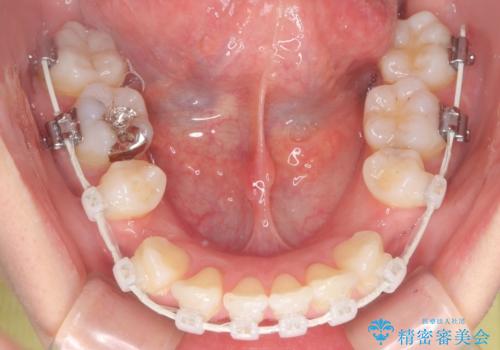

- 審美装置

- 出っぱによる口元の閉じにくさを主訴に来院されました。上顎の出っ歯と上下顎叢生も認められたため、上下顎両側4番抜歯を行い、ワイヤー矯正で治療する治療計画を立てました。

上顎にはMI(マイクロインプラント)を埋入して固定源とすることで出っ歯の改善を図りました。

少しスペースクローズに時間がかかりましたが、MIを用いたワイヤー矯正で

主訴である出っ歯と叢生が改善されました。口も閉じやすくなり、スッキリとした口元になりました。